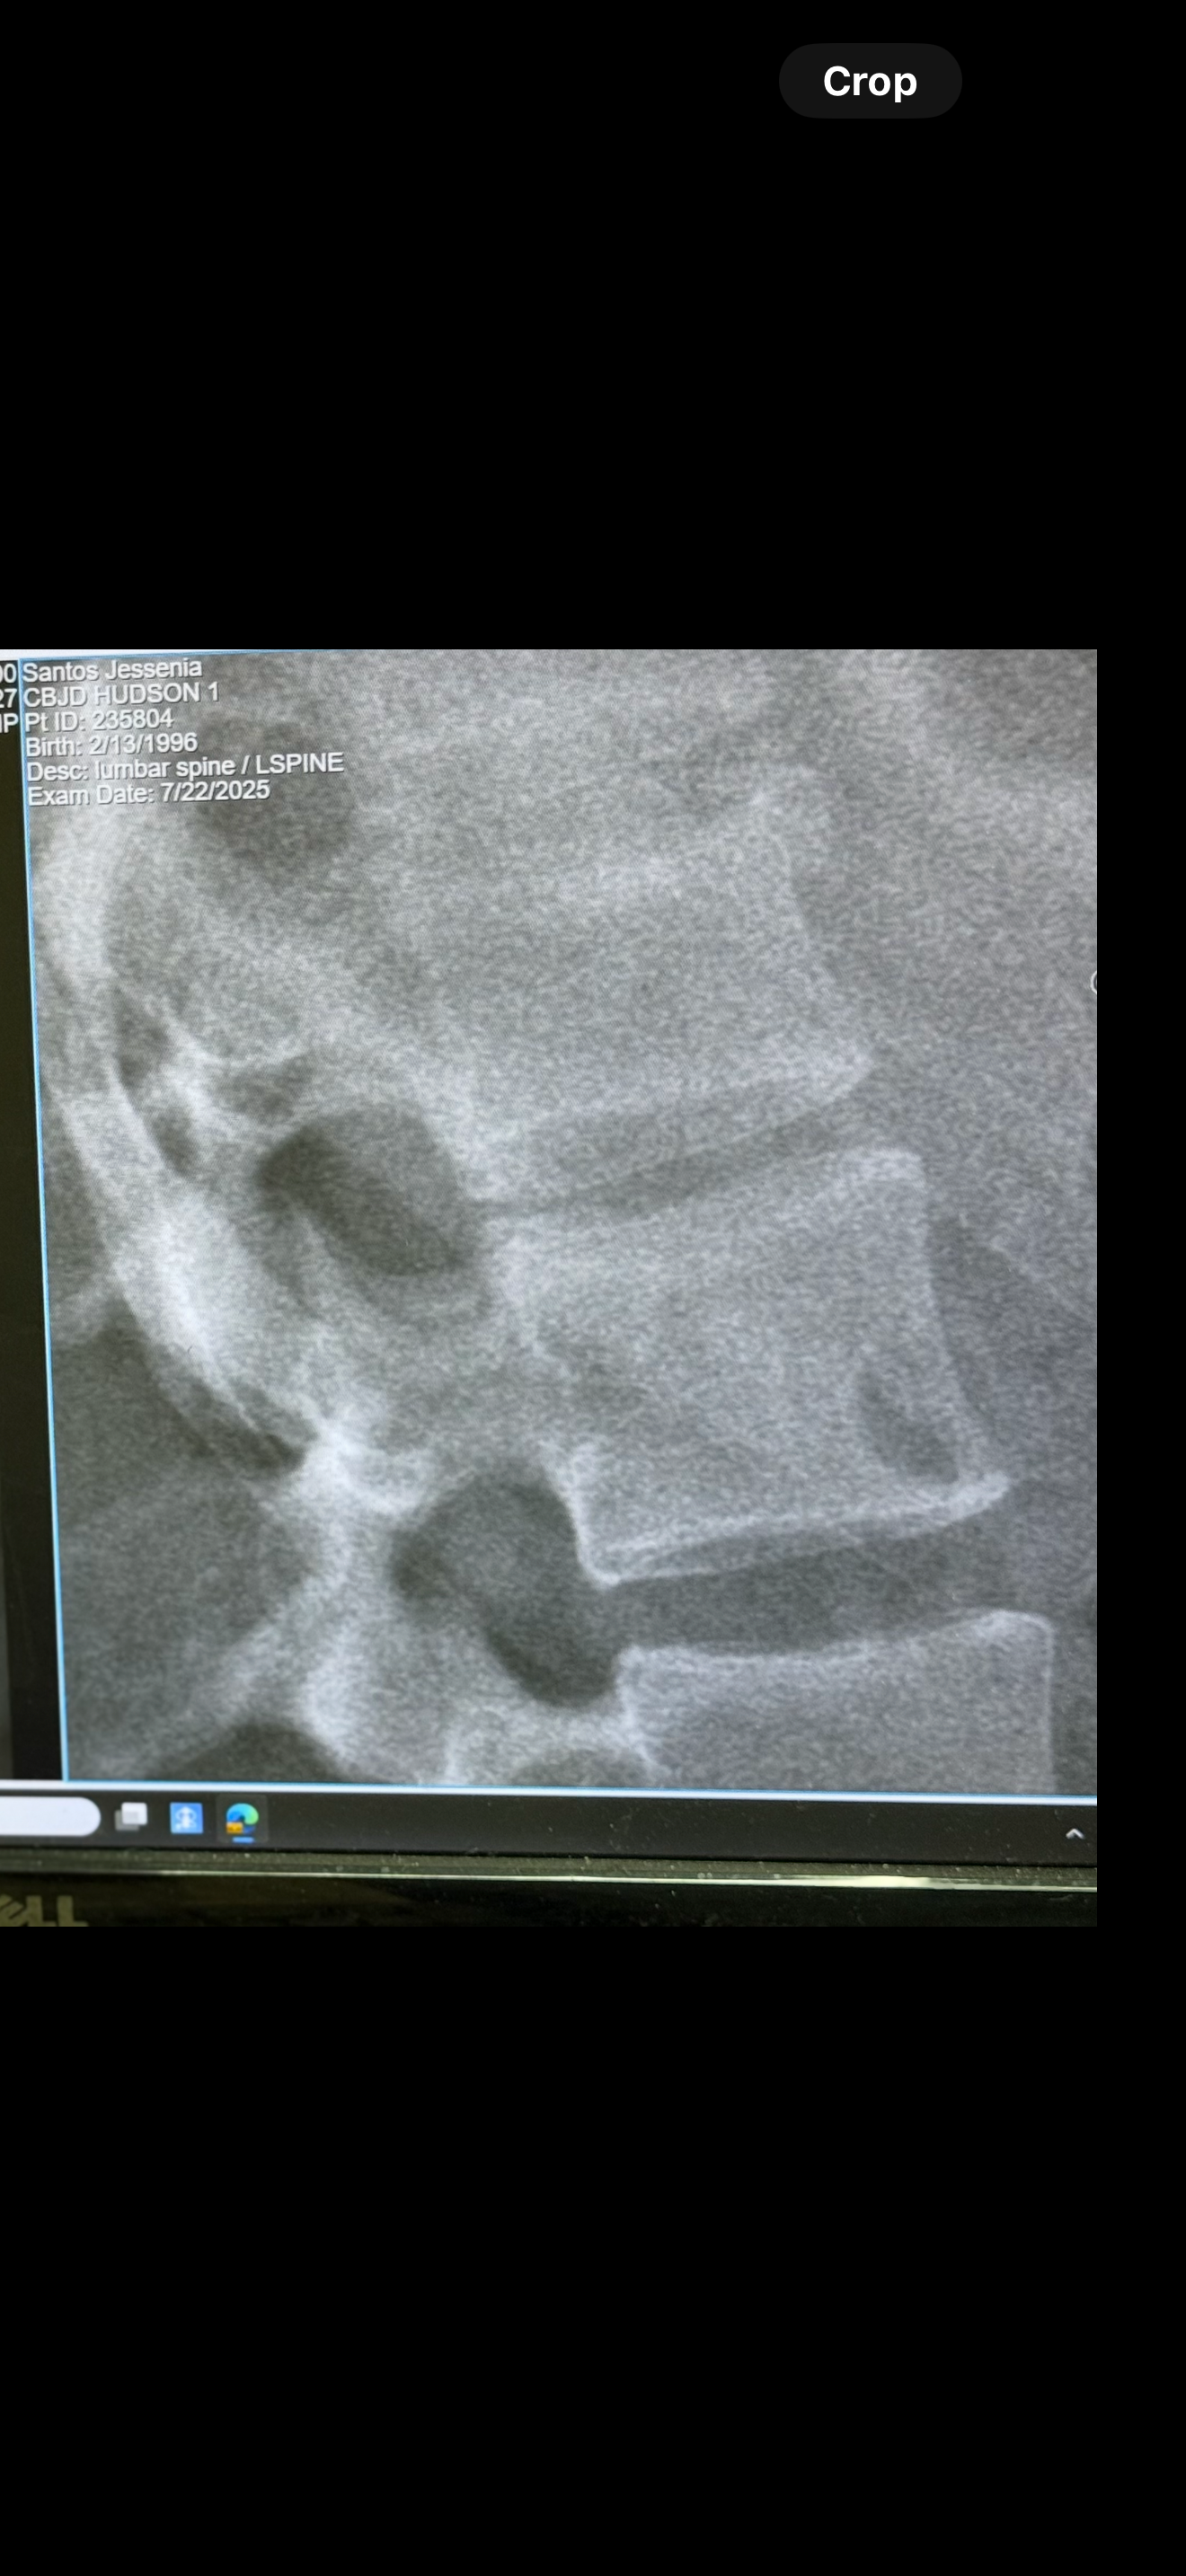

About two weeks ago, Jess slipped and fell down 16 steps of stairs. Unfortunately, she has two compression fractures (T12 and L1) from falling down the stairs. Her doctor told her he would like to fix these fractures by doing a kyphoplasty (a minimally invasive procedure). Unfortunately, her insurance doesn’t want to pay for it. They said she does not meet medical necessity, which is ridiculous since she has two fractures in her vertebrae. They expect her to sit home for three to four months with a back brace and pain meds and let it heal on its own.